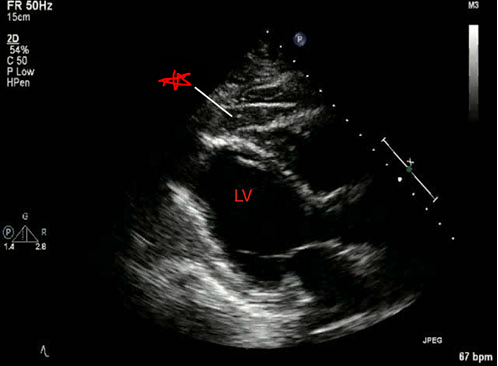

What condition is seen in this 2D image?

Cardiac tamponade